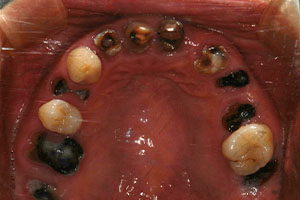

치료증례 전후사진

Before & After